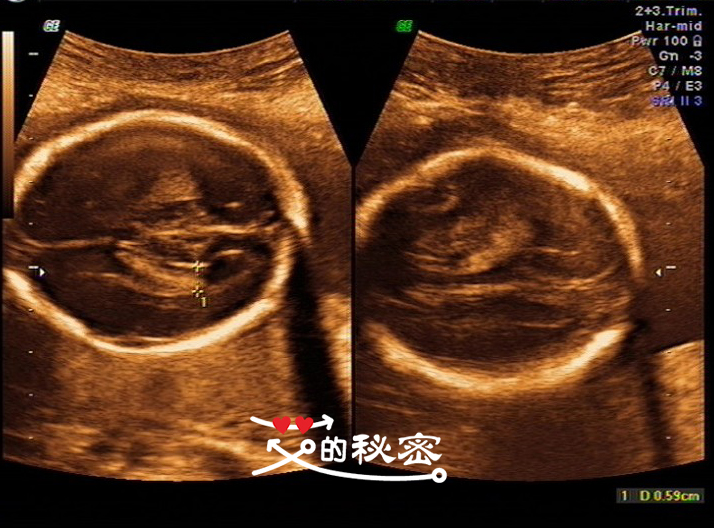

5、胎儿头部:颅骨环未见明显缺损,大脑回声可见,脑中线居中,两侧丘脑可见,侧脑室未见增宽,小脑形态未见异常,小脑蚓部可见,后颅窝未见增大。英文的意思:CEREB小脑横径。